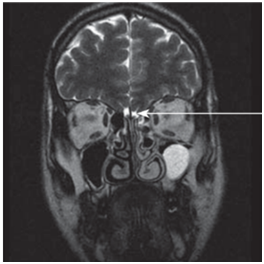

A 15years old girl was referred to the ENT Department of our hospital with a history of a lifelong impossibility to perceive smells She also complained of abundant rhinorrhea and occasional headaches. She didn’t have any relevant family history and had a normal physical and psychological development. Rhinoscopy and fiberoscopy showed no structural abnormalities, no septal deviation, polyps nor any other inflammatory findings that could justify the symptoms. The olfactometry using the University of Pennsylvania Smell identification Test (UPSIT) described a total anosmia. Magnetic Resonance Imaging (MRI) found the absence of olfactory bulbs and a hypoplasia of both olfactory sulcus, more severe on the left one (Figure 1). Due to these findings, were referred our patient to the Endocrinology and Gynecology Departments of our hospital, where they determined a normal hormonal and sexual development. Thus the diagnosis of isolated congenital agenesis of the olfactory bulbs and hypoplasia of olfactory sulcus was made.

Figure 1Coronal section T2-wheigted MRI though the anterior skull base of the index case. Absence of olfactory bulbs (blue arrows).

1. Hypo plastic left olfactory sulcus (white arrow).

2. Coronal section T2-wheigted MRI though the anterior skull base of a normal patient. Olfactory bulbs (white arrow). Taken from Carswell.6